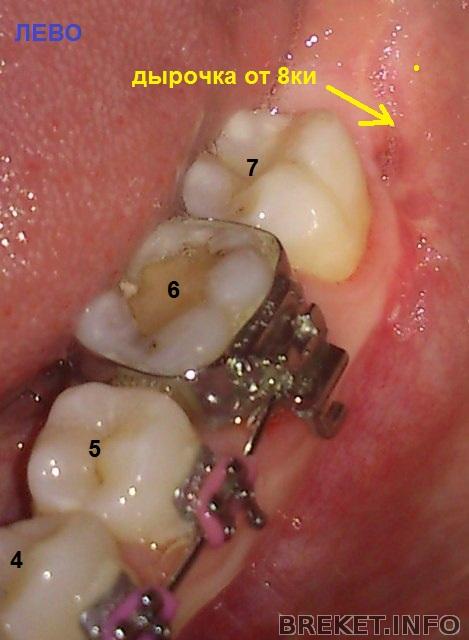

тем, кто помнит мою историю про , добавляю последствия) слева была удалена только 8ка, справа удалена восьмерка и дважды лазили искать ископаемые

слабонервным - форбидден!

А куда уехал центр?? Мда и шрамы "милые". Как же я рада, что мне не пришлось удалять мудрости